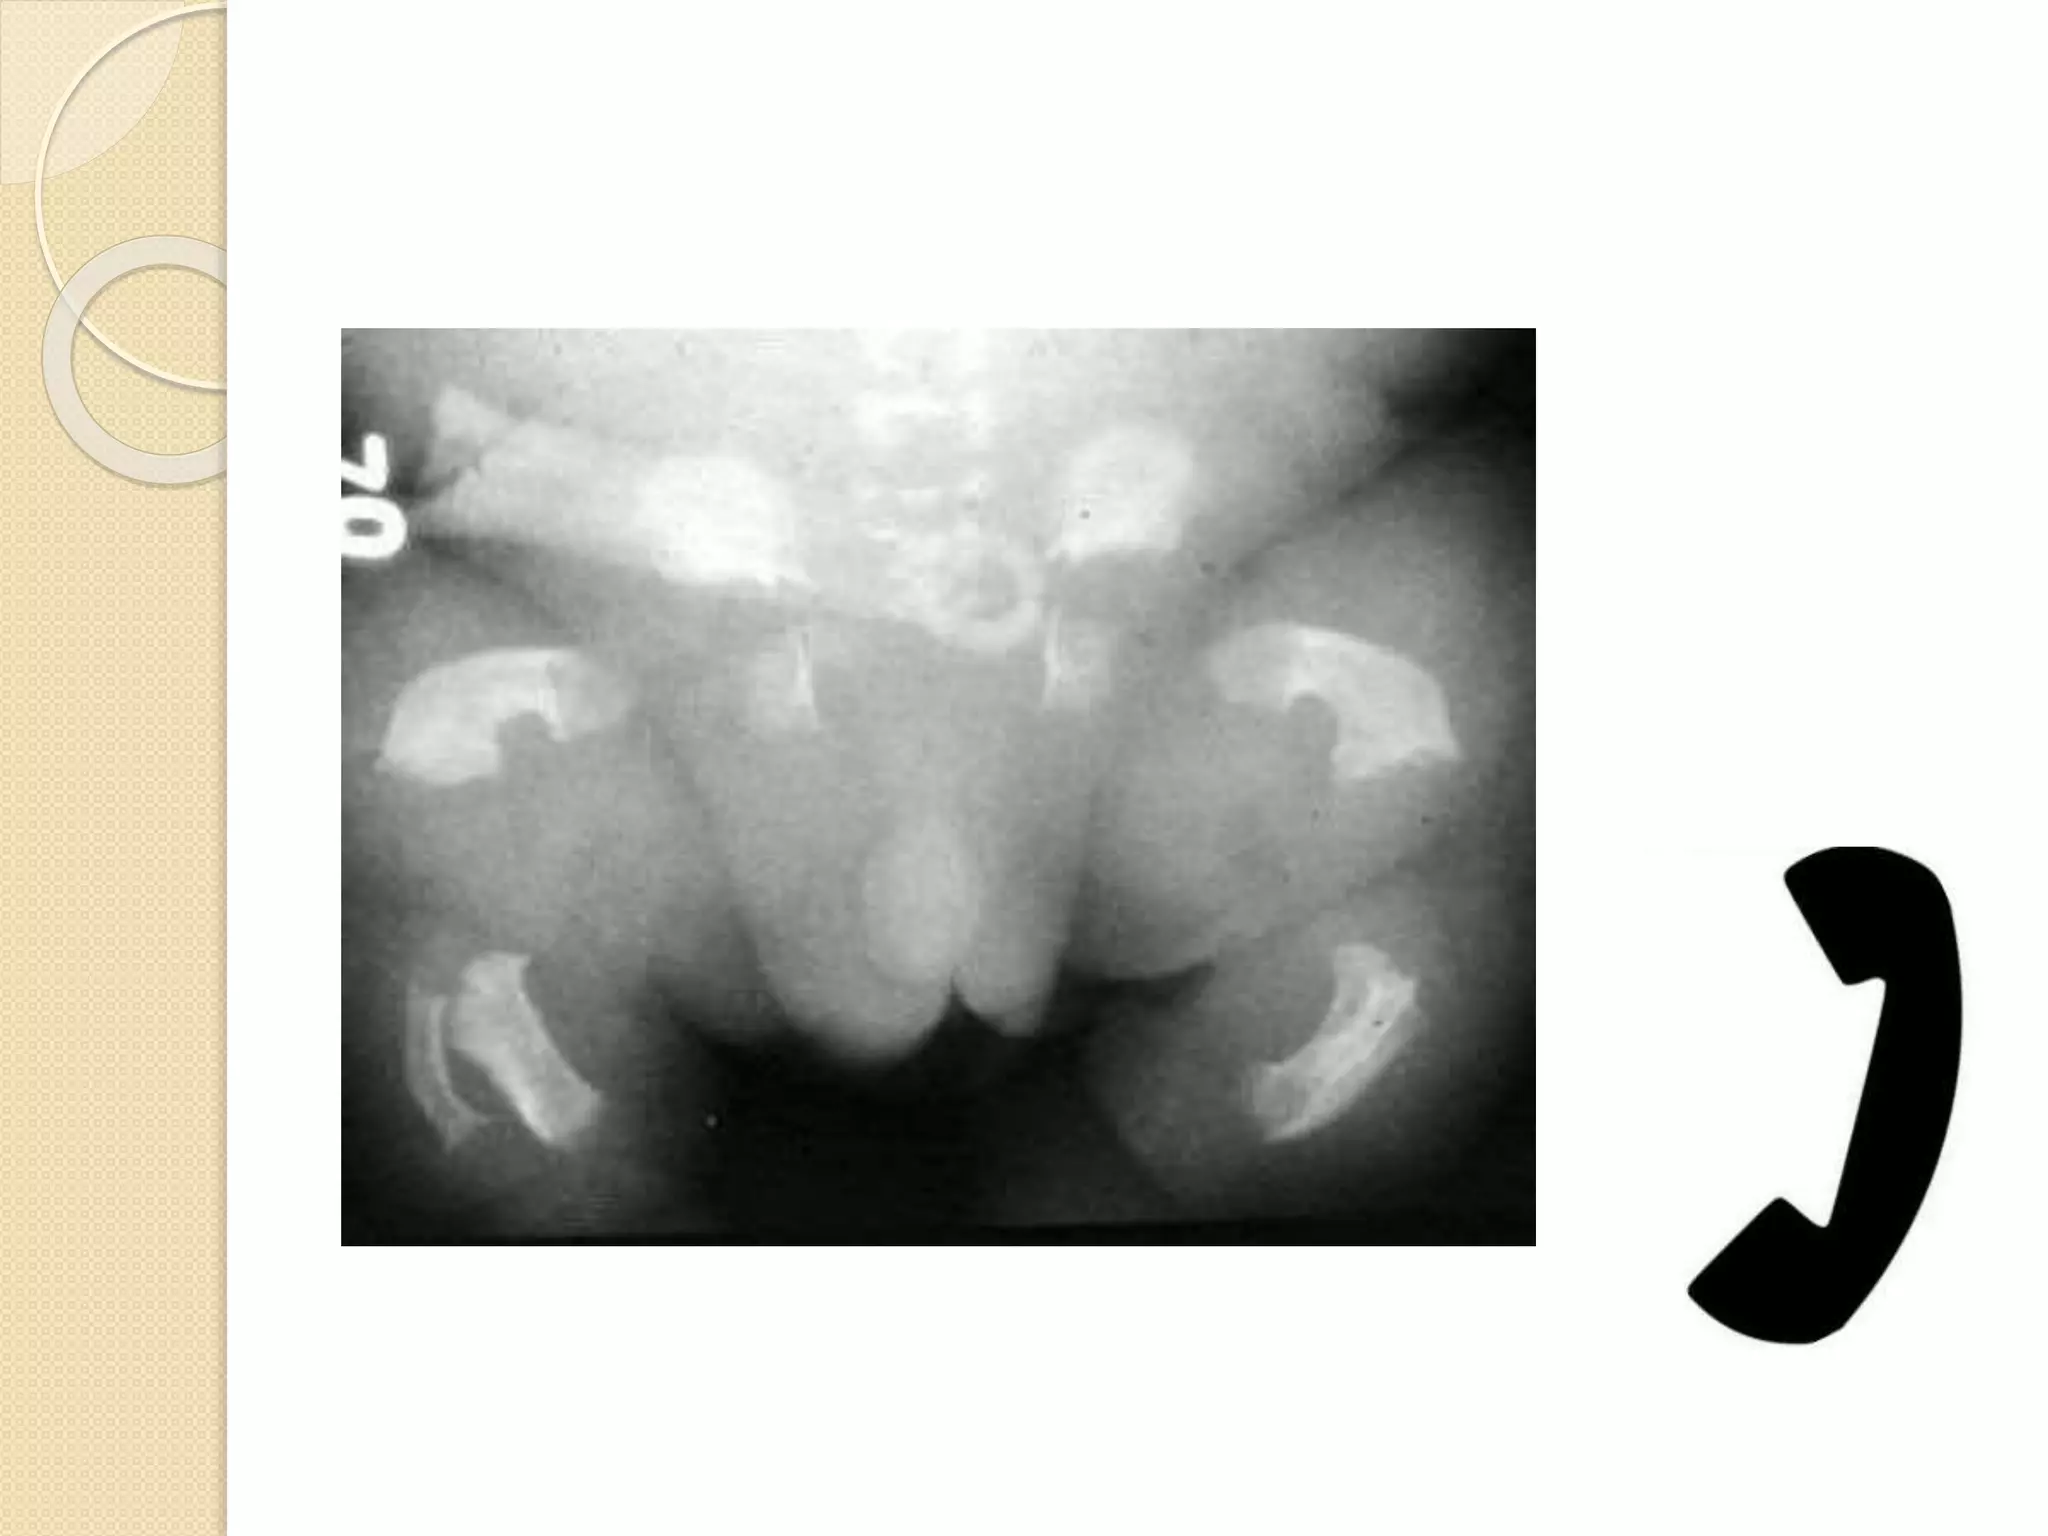

 Strippling / punctate calcification

tarus, carpus, long bone epiphysis,

vertebral transverse process, ischium

& pubis

 Soft tissue calcification around the

joints present